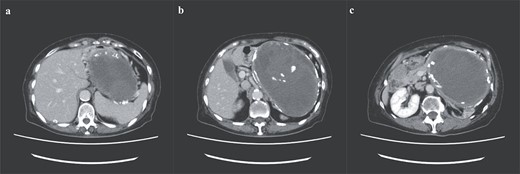

A 74-year-old Asian woman had been treated for diabetes mellitus but had stopped treatment on her own. The HbA1c level increased sharply to 16%. Blood samples showed no abnormal findings such as elevated levels of tumor markers (Table 1). There was no history of abdominal imaging, sudden abdominal pain, abdominal trauma, or abdominal surgery. Contrast-enhanced abdominal computed tomography (CT) revealed a large hematoma-like cystic lesion in the pancreatic tail (Fig. 1a–c). Calcification of the wall and internal septum was prominent. Magnetic resonance imaging (MRI) demonstrated a 156 × 112 mm marginal T1W high signal (Fig. 2a) and an internal T2W uneven low signal (Fig. 2b) on the dorsal side of the stomach, suggesting a hematoma-like cystic lesion. Diffusion showed a high signal intensity, but abnormal enhancement was not observed (Fig. 2c). Considering the possibility of intra-abdominal dissemination of the cystic tumor via a puncture, the patient underwent distal pancreatectomy and splenectomy with lymph node dissection for diagnostic and therapeutic purposes. The cyst wall adhered strongly to the surrounding tissue (Fig. 3); however, no adverse events were noted during the operation. The operating time was 7 h 19 min, and blood loss was 809 ml. The patient was discharged 11 days postoperatively, with a good postoperative course.

Preoperative abdominal enhanced MRI showing a 156 × 112 mm marginal T1W high (a) and an internal T2W uneven low signal (b); diffusion shows some high signal, but abnormal enhancement cannot be noted (c).